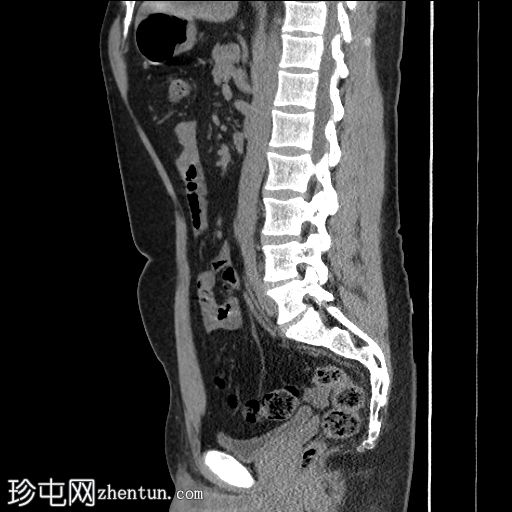

矢状位

平扫

左下腹降结肠旁可见卵圆形脂肪密度影,边缘密度略高,邻近脂肪组织呈条索状改变(冠状位和矢状位)。

未见肾结石或输尿管结石。

未见腹腔内游离气体或液体。